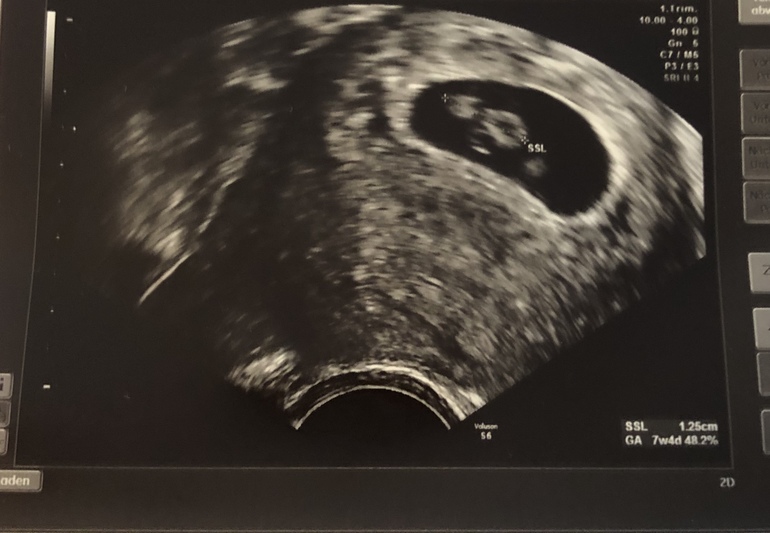

СамочувствиеМалыш подрос, 1,25 см, сердце пульсирует.

Она сначала замеряла как-то по-другому, там срок был 6+6, я немного напряглась.. потом с другого ракурса 1.25 намеряла)